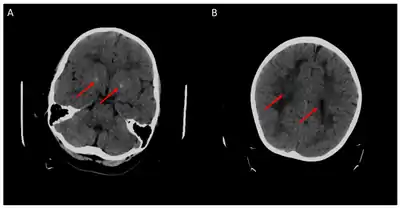

Children with the FOLR1 mutation are born healthy. Symptoms typically appear at about 5 to 24 months of age. The symptoms get worse with time. Without treatment there may be poor muscle tone, trouble with coordination, trouble talking, and seizures.[2][3] In addition, signs of psychomotor retardation, sleep disturbances, cerebellar ataxia, and delayed development of head growth can occur. At around age three, visual disturbances can develop, and sensorineural hearing loss can occur at around age six.[11] In children with cerebral folate deficiency, the cerebrospinal fluid shows low levels of 5MTHF, and a loss of white matter in the brain (leukodystrophy) may occur. As a result of the decreased levels of 5MTHF, the child experiences low levels of Vitamin B folate.[12] There is inability for the 5MTHF to be transported across the blood-brain barrier, resulting in symptoms of seizures, delayed cognitive and motor processing, and autistic features.[13]